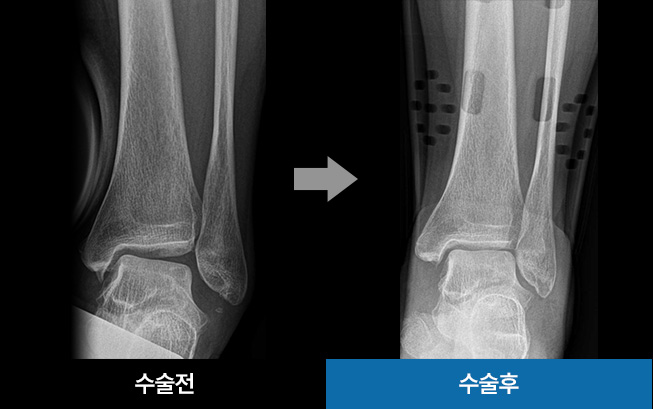

이 수술은 틀어진 발목을 바로잡아 통증을 감소시키고

관절의 부담을 덜어주는 것을 목표로 합니다.

발목 연골 한쪽만 닳아 발생하는 발의 기울어짐을 교정하고,

손상된 연골 부위의 압력을 줄여주기 위해 체중이 정상적인

연골 부위로 분산되도록 축을 이동시키는 수술법입니다.

수술시간 약 1시간

발목 압력 해소 기대